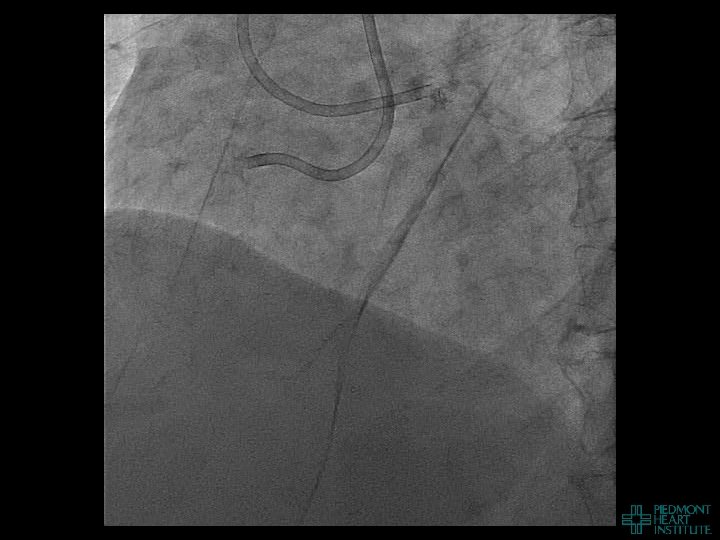

Case Example 3